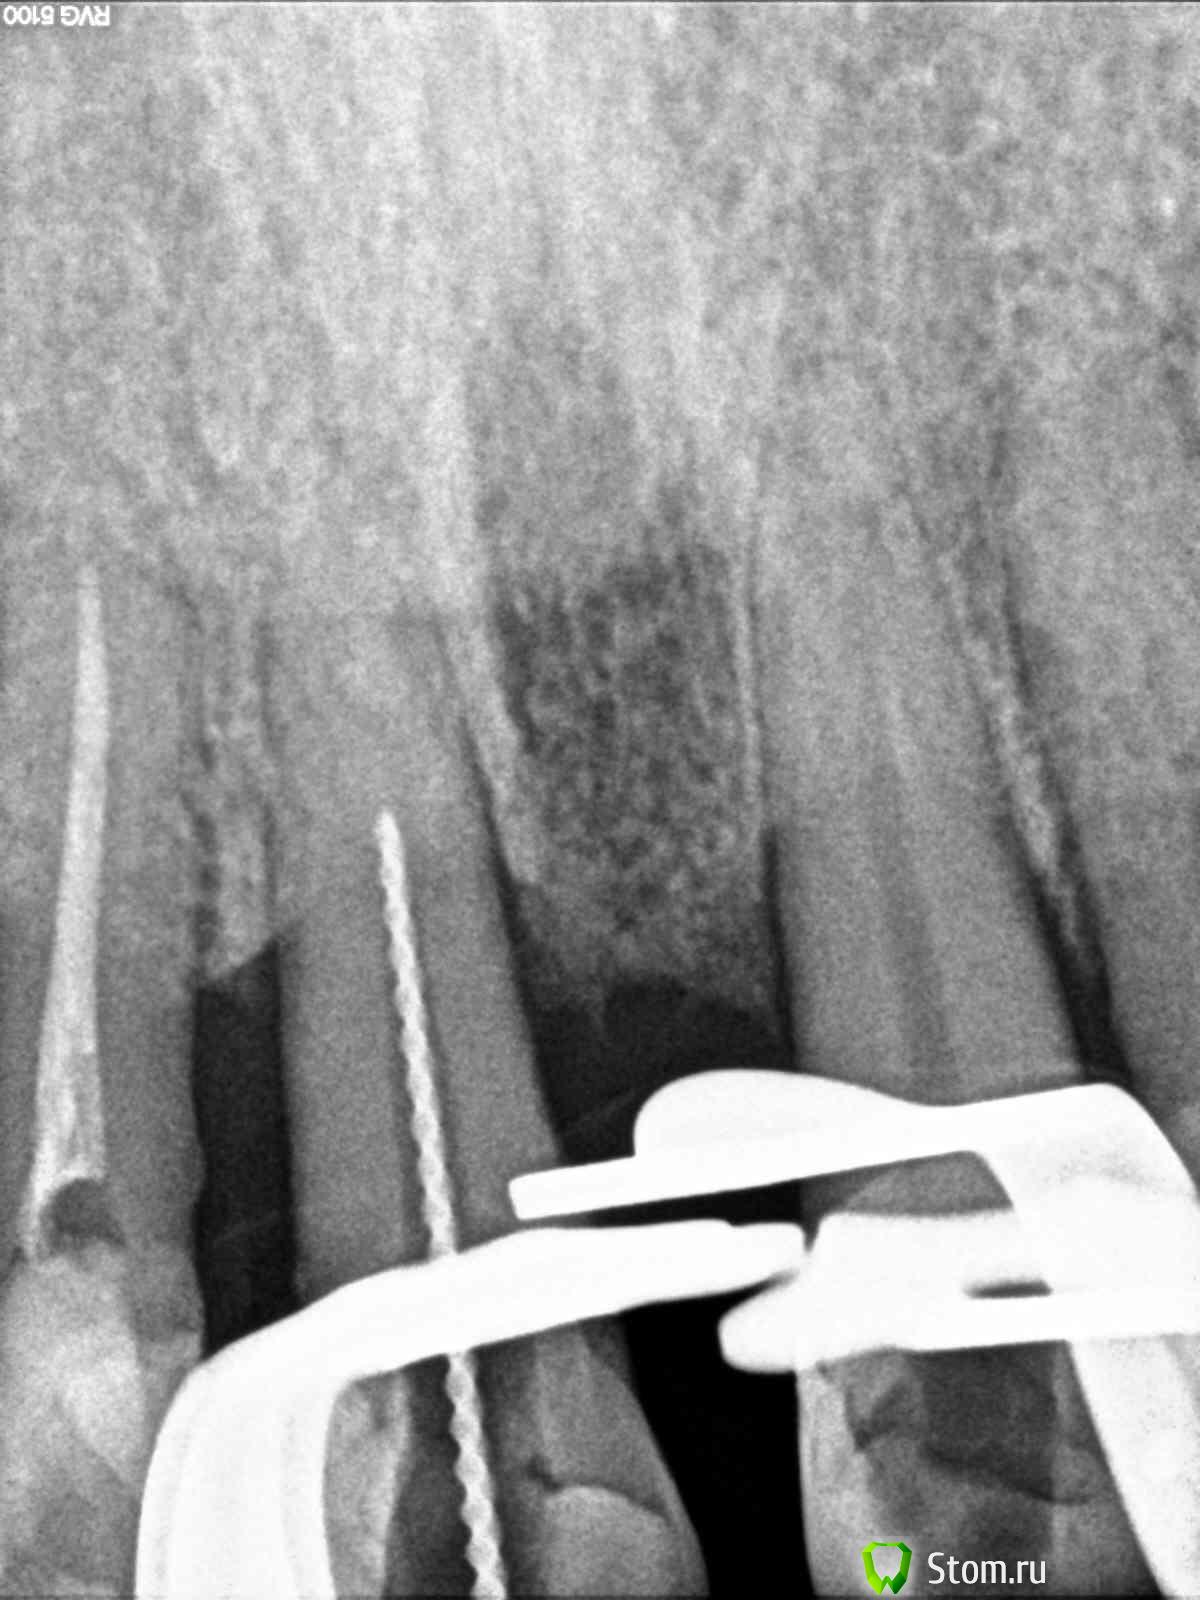

Magdalena Опубликовано 31 января, 2012 Поделиться Опубликовано 31 января, 2012 (изменено) В одном из филиалов стоял микроскоп, случайно узнала, что никто им не работает, забрала себе.)На удаленных зубах потренироваться не успела - попались ситуации, когда скоп был нужен сразу в работе.1. Пациент 66 лет, перелечивание зуба 1.1 под коронку. По КТ - канал запломбирован чуть более 1\2 длины, на верхушке корня очаг разрежения костной ткани с нечеткими границами (КТ фоткала с экрана компьютера, не смогла скопировать ) В первое посещение - распломбировала канал на проходимую длину (в канале гутта), инструмент дальше не идет абсолютно, по КТ хода канала после пломбировочного материала не увидела.Оставила в канале раствор ЭДТА на неделю, пломба Витремер.Во второе посещение еще раз смотрю КТ - смущает меня все-таки такое разрежение, вроде тоооненько прослеживается ход канала. Все отмыла, привезла скоп - на "дне" канала увидела белую точку. Т.к. опыта лечения под микроскопом у меня не было - подумала что это блик, посмотрела под разными увеличениями - все-равно есть, решила пройти по точке УЗ - и сразу же провалилась ( и сердце упало тоже ) Канал при первичном эндо был заступенен.Пломбирование 2. Пациент 35 лет, перелечивание зуба 1.4 под коронку. КТ : каналы запломбированы на 1\2, расширение периодонтальной щели в обл. верхушек корней.щечный каналнебный каналСняла пломбу - в каналах - фосфат-цемент. Сразу привезла микроскоп, распломбировывала УЗ под контролем скопа.Снимок с файлами скинуть забыла Во второе посещение пломбирование, АЛ на этом уровне показывает верхушки Сейчас мне привезли зеркала, специально для микроскопа. В одном наборе стомат. зеркало обычное с увеличением и стомат. зеркало без увеличения, а также маленькие зеркала собственно совсем без зеркальной поверхности... В интернете инфу по ним не нашла, подскажите, плиз, как их использовать. Изменено 31 января, 2012 пользователем Magdalena Ссылка на комментарий

DokDent Опубликовано 2 февраля, 2012 Поделиться Опубликовано 2 февраля, 2012 http://forum.stom.ru/uploads/monthly_01_2012/post-15805-0-28919800-1328031541_thumb.jpg Ань,посмотри апикальный уровень обтурации корневого канала. Ссылка на комментарий

Magdalena Опубликовано 3 февраля, 2012 Автор Поделиться Опубликовано 3 февраля, 2012 (изменено) Ань,посмотри апикальный уровень обтурации корневого канала.Ирин, пломбировка до апекса...считаешь не плотно в апикальной трети? Апикальный упор на 0,5 мм, апекс не разбивала Изменено 3 февраля, 2012 пользователем Magdalena Ссылка на комментарий

DokDent Опубликовано 3 февраля, 2012 Поделиться Опубликовано 3 февраля, 2012 Ирин, пломбировка до апекса...считаешь не плотно в апикальной трети? Апикальный упор на 0,5 мм, апекс не разбивала Ань,на мой взгляд-да. Ссылка на комментарий

Magdalena Опубликовано 3 февраля, 2012 Автор Поделиться Опубликовано 3 февраля, 2012 Ань,на мой взгляд-да.Сейчас сидела - разглядывала - кажется действительно не плотно Посмотрю еще снимок ортопеда, после подготовки под штифтовкладку. Ссылка на комментарий